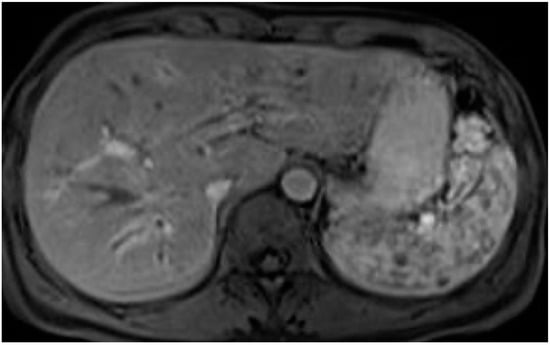

5. Technical Aspects of MRI in PSC

6. Cholangiographic and Liver Parenchymal Changes in PSC